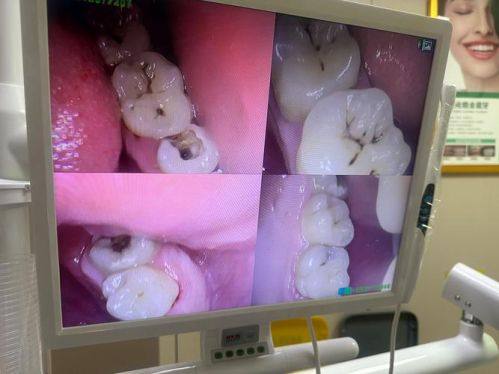

补牙材料的选择也会在一定程度上影响补完牙后牙齿的情况。目前市面上的补牙材料有特别多种,比如树脂材料、玻璃离子材料等。不同的补牙材料有不同的特点和适用情况。树脂材料的颜色和牙齿比较接近,美观度高,而且粘结性好,能良好地与牙齿贴合,不容易出现缝隙,这样可以减少细菌滋生的机会。玻璃离子材料对牙齿有一定的防龋作用,价格相对较低,但它的耐磨性和美观度可能不如树脂材料。所以,在选择补牙材料时,我们要根据自己的牙齿情况和需求,在医生的建议下做出合适的选择。合适的补牙材料可以更好地保护牙齿,降低牙齿再次龋坏的风险。